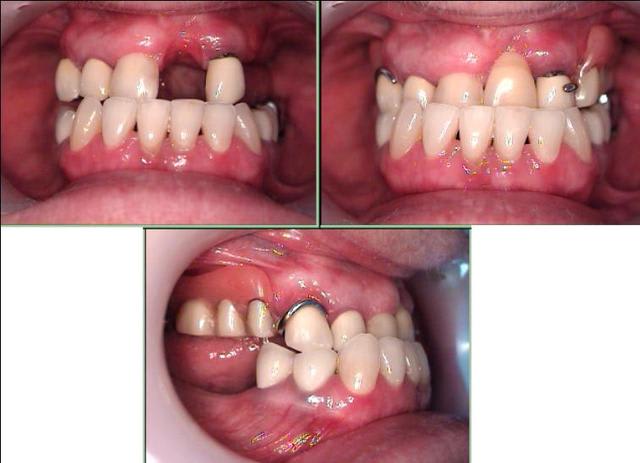

Un antre cas, pour faire plaisir à Jeff2 et montrer que le recentrage n'est pas systématique.

Après avoir fait ouvrir grand, bien relaxé la patiente, elle restait dévié en ouverture max, et fermait direct en dévié : donc, j'ai choisi de reconstruire sans recentrer. ( les recentrages et propulsions que j'ai pu réalisé en technique clausade, pourtant validé en posturo, ne m'ont jamais vraiment satisfait )

J'ai augmenté la DV pour retrouver une classe 1. Mais je ne sais pas si je vais pouvoir finir ainsi ou refaire une classe 3, car même si elle me dit que tout le monde la trouve changé en mieux, elle me dit a chaque RV, qu'elle a toujours eu le menton en avant, et que ce n'est pas possible de faire autrement !

la 11 étant plus étroite que la 21, tu peux gagner un bon millimètre à 1/ 1/2 sur le centrage,en augmentant sa largeur,(je ne parle que de l'esthétique)